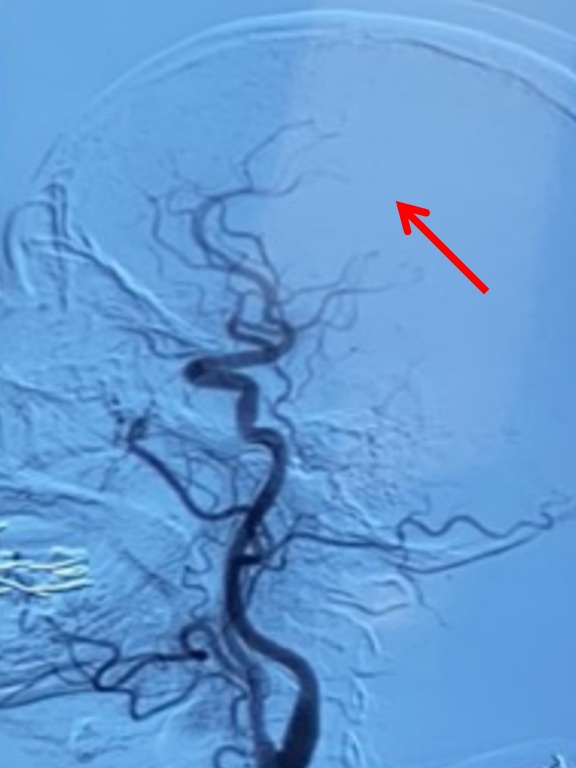

观察20分钟前向血流维持良好且右侧大脑前动脉显影。

左侧颈内动脉造影双侧大脑前动脉显影良好。结束手术。